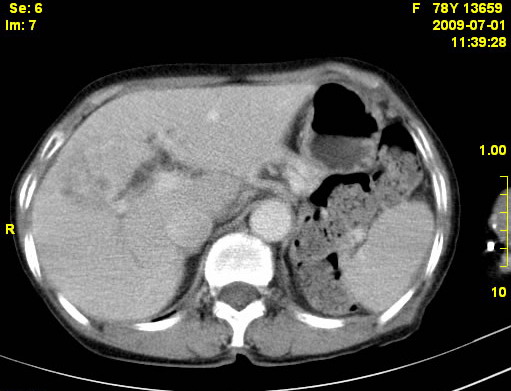

以下是引用zjzjr在2009-7-3 11:02:00的发言:[br]动脉期不均匀强化,门脉期及延迟期强化明显,肝门部见肿大淋巴结影,肝内胆管扩张.考虑肝右叶前段胆管细胞癌伴肝门淋巴结转移,胆内胆管扩张.慢性胆囊炎.

以下是引用dsl555在2009-7-4 10:59:00的发言:[br]考虑肝右叶前段胆管细胞癌伴肝门淋巴结转移,胆内胆管扩张.慢性胆囊炎. [br][br]支持。